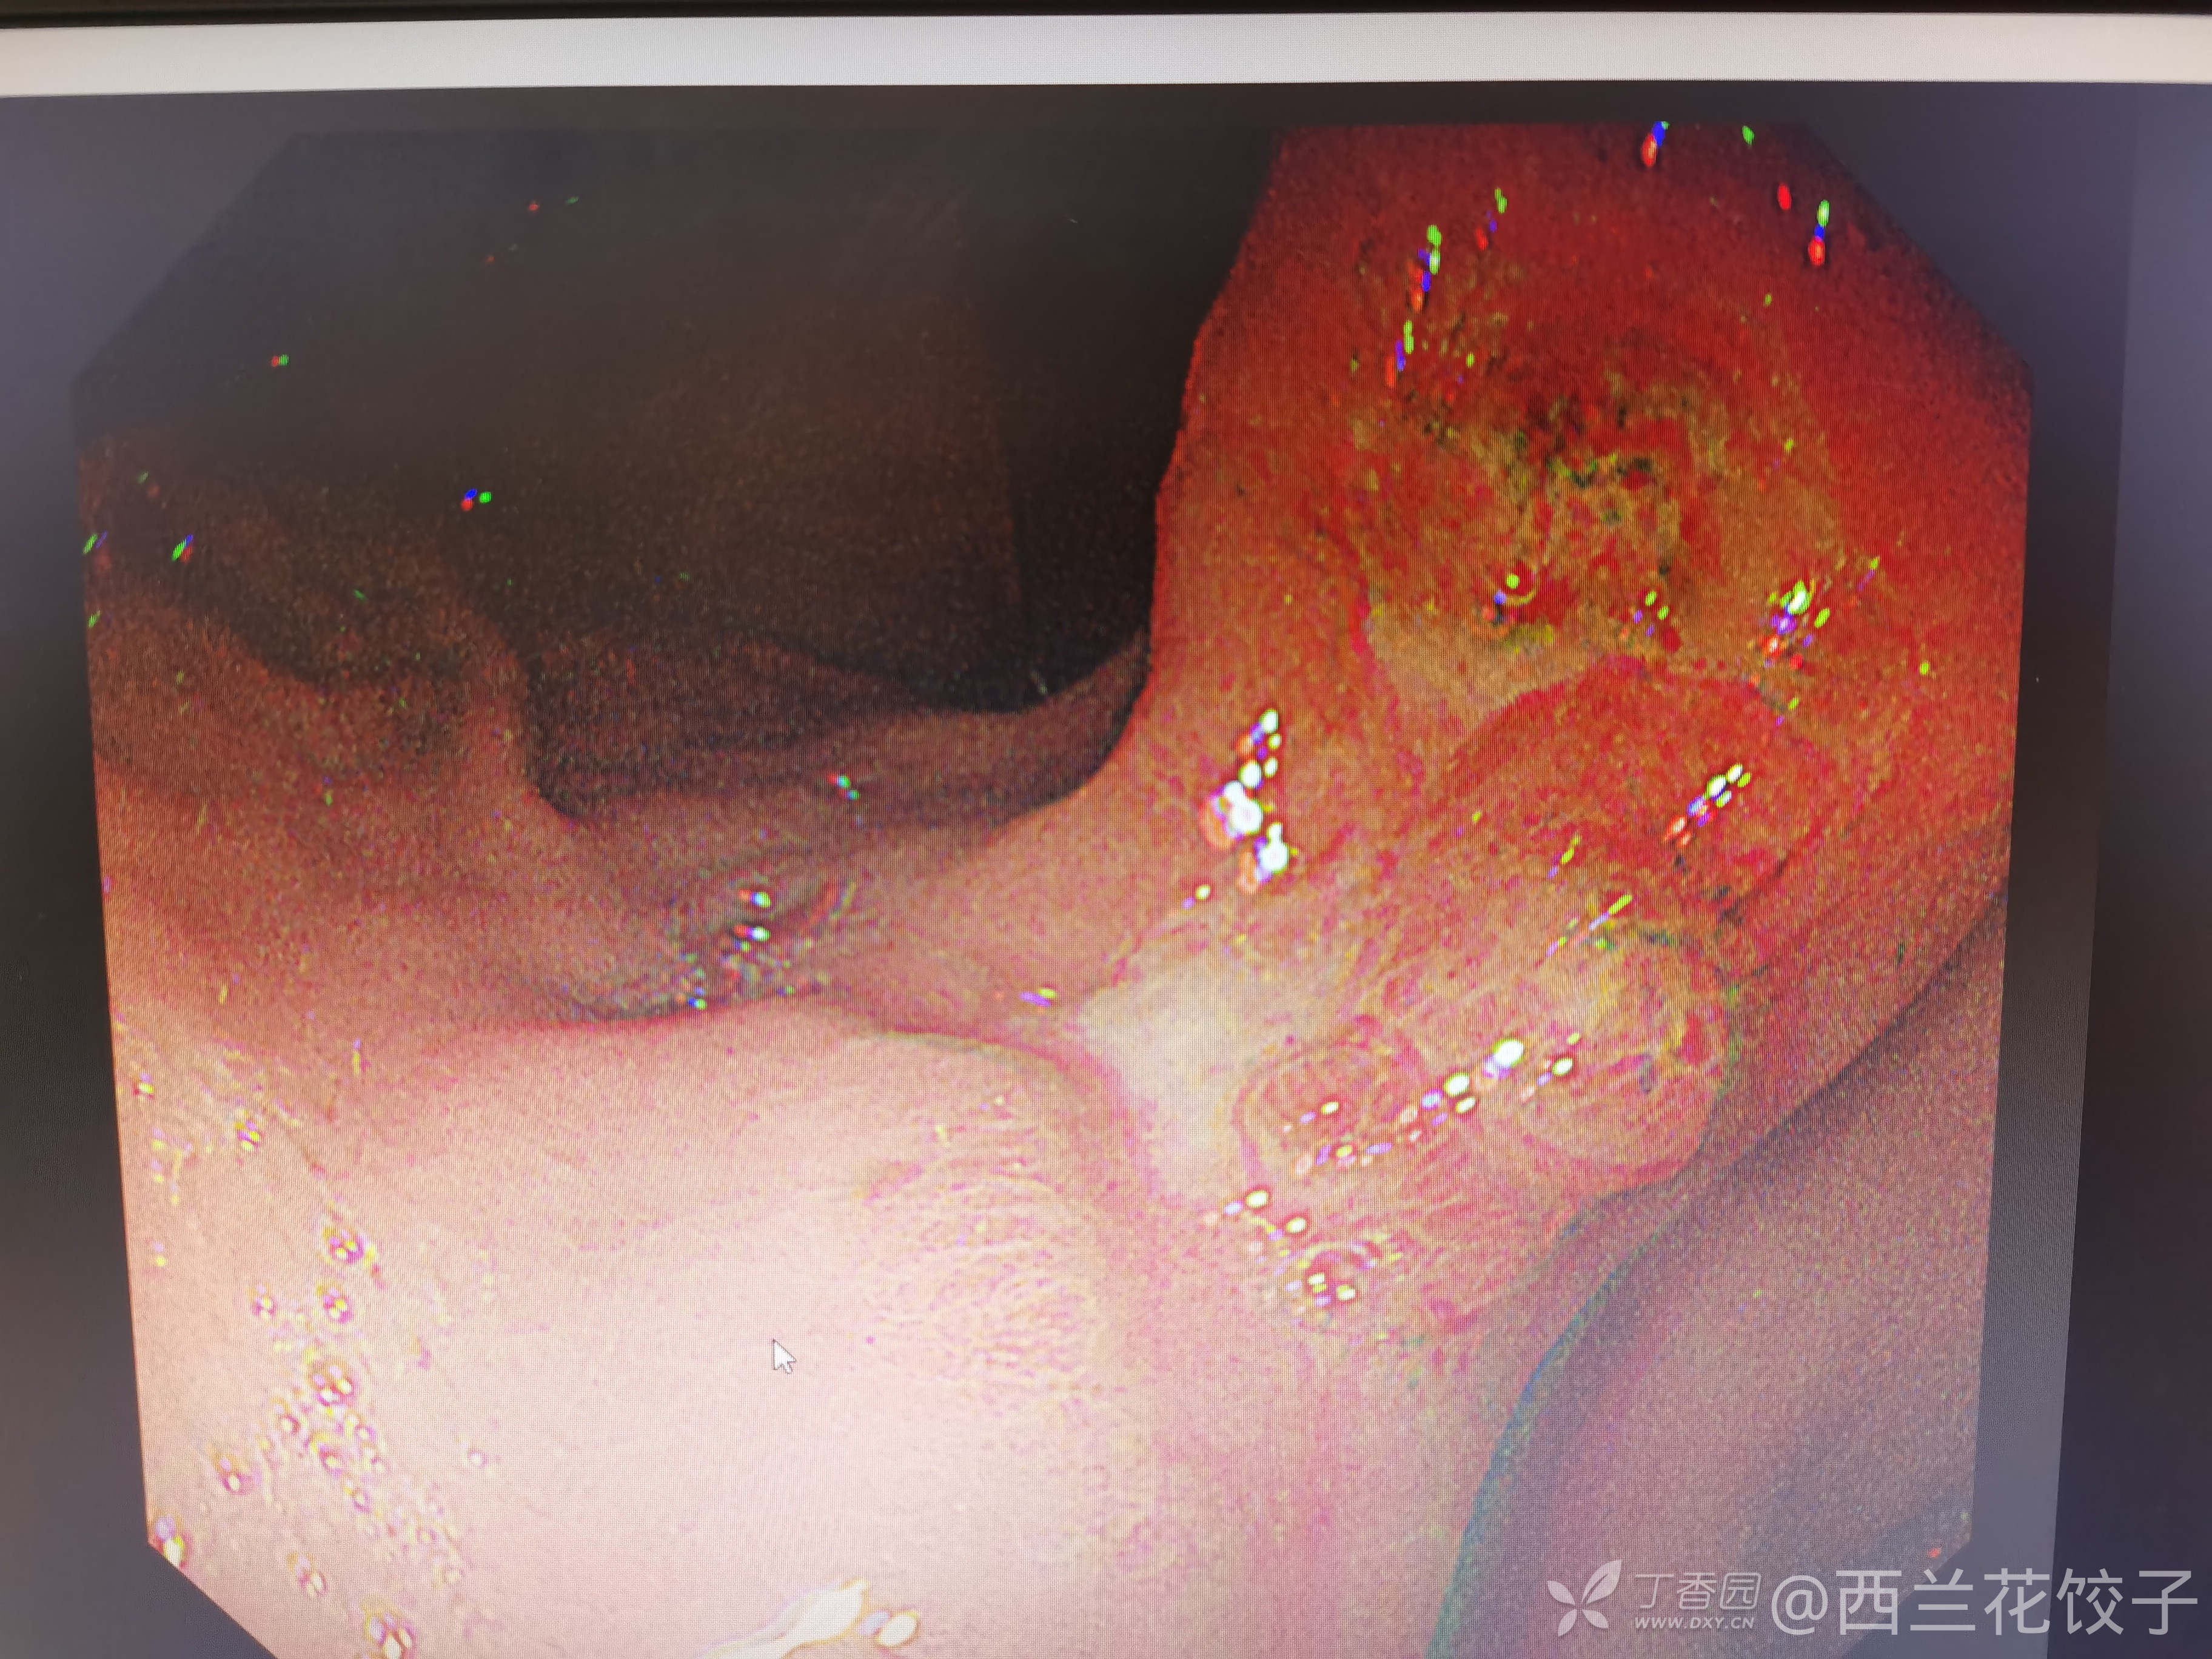

胃角巨大溃疡,进展期Ca?

患者性别:男

患者年龄:60岁

主诉:上腹部疼痛2年余加重要1周

简要病史:2年来出现上腹部疼痛,平时喜饮酒,近1周疼痛加剧,黑便来诊。

讨论:内镜如下进展期Ca?后期如何治疗?